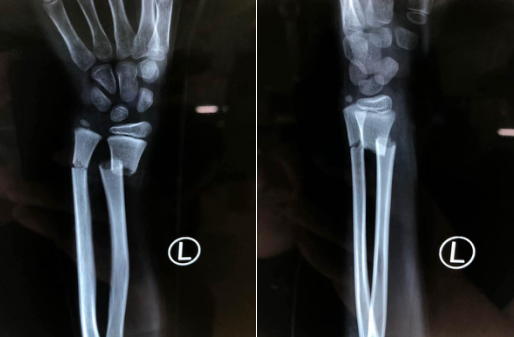

于是男孩的父母立刻带着男孩来到betway在线登陆就诊,X光片显示男孩左尺桡骨远端骨折,骨折移位明显。

明确手术方案后,熊祖国医师为男孩安排了手术,术中在助手牵拉对抗下牵引予以复位左尺桡骨骨折端,各以两根金属骨针交叉打入内固定,术中一切顺利,术后复查x线片,见各骨折复位良好,内固定在位。